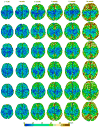

Quantitative measurement of the dynamic longitudinal cortex development during early postnatal stages is of great importance to understand the early cortical structural and functional development. Conventional methods usually reconstruct the cortical surfaces of longitudinal images from the same subject independently, which often generate longitudinally-inconsistent cortical surfaces and thus lead to inaccurate measurement of cortical changes, especially for vertex-wise mapping of cortical development. This paper aims to address this problem by presenting a method to reconstruct temporally-consistent cortical surfaces from longitudinal infant brain MR images, for accurate and consistent measurement of the dynamic cortex development in infants. Specifically, the longitudinal development of the inner cortical surface is first modeled by a deformable growth sheet with elasto-plasticity property to establish longitudinally smooth correspondences of the inner cortical surfaces. Then, the modeled longitudinal inner cortical surfaces are jointly deformed to locate both inner and outer cortical surfaces with a spatial-temporal deformable surface method. The method has been applied to 13 healthy infants, each with 6 serial MR scans acquired at 2 weeks, 3 months, 6 months, 9 months, 12 months and 18 months of age. Experimental results showed that our method with the incorporated longitudinal constraints can reconstruct the longitudinally-dynamic cortical surfaces from serial infant MR images more consistently and accurately than the previously published methods. By using our method, for the first time, we can characterize the vertex-wise longitudinal cortical thickness development trajectory at multiple time points in the first 18 months of life. Specifically, we found the highly age-related and regionally-heterogeneous developmental trajectories of the cortical thickness during this period, with the cortical thickness increased most from 3 to 6 months (16.2%) and least from 9 to 12 months (less than 0.1%). Specifically, the central sulcus only underwent significant increase of cortical thickness from 6 to 9 months and the occipital cortex underwent significant increase from 0 to 9 months, while the frontal, temporal and parietal cortices grew continuously in this first 18 months of life. The adult-like spatial patterns of cortical thickness were generally present at 18 months of age. These results provided detailed insights into the dynamic trajectory of the cortical thickness development in infants.